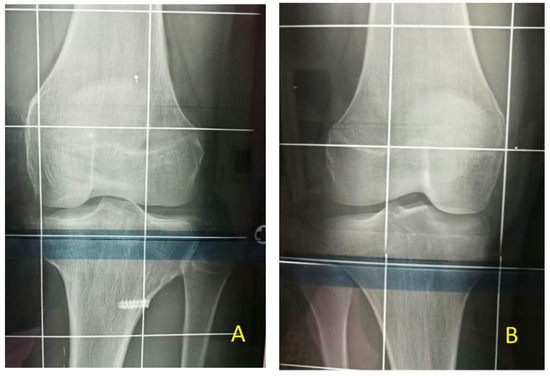

At the time of the first surgical procedure, mean age was 7.94 years (range 2.91–14.41) and mean LLD was 3.65 cm (range 2–10). TE was performed either on the growth plate of the proximal tibia (PTE) and on the growth plate of the distal femur (DFE) (Figure 4, Figure 5 and Figure 6). Due to the different distribution of LLD with the tibia more and early involved, usually the first step was to treat proximal tibial growth plate, then followed by the distal femur in a second surgical procedure (Figure 6). If LLD was very severe at first evaluation or if growth potential was very high during clinical follow-up, PTE and DFE were performed in one step at the same time (Figure 7). If, during guided growth treatment lower limb axial deviation (varus-valgus deformity) occurs, further surgical procedures were necessary, such as removal and changing of the implants (Figure 8), proximal tibia hemiepiphysiodesis (PTHE) or distal femur hemiepiphysiodesis (DFHE) (Figure 9).

Figure 4. BWS (Beckwith-Wiedemann Syndrome) male patient with LLD (leg length discrepancy) left at age of 6 years: (A) for clinical evaluation, medial knee joint rime (whole lines) and medial malleolus (dotted line) of both legs are signed; only mild length discrepancy of femurs but severe discrepancy of tibias are present; (B) in external rotation of both lower extremities LLD is clearly visible; (C) postoperative X-ray in antero-posterior projection showing performed PTE (temporary proximal tibia epiphysiodesis) with implanting of one plate and two screws for medial and one plate and two screw for lateral aspects of growth plate respectively to stop growing of proximal tibia (8-plateR, Eight Plate Guided Growth System+, Orthofix Medical Inc.© Lewisville, TX (USA)).